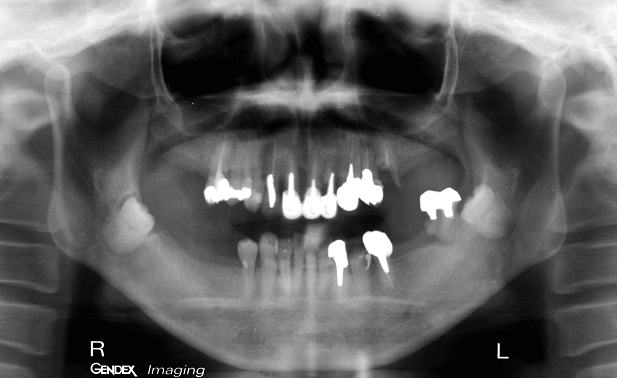

精密検査(診査診断・治療計画)

なぜこのような状態になってしまったのか?どうしたら治るのか?長期に安定させるにはどうしたら良いのか? 徹底的に検査し治療計画を立案します。 |

問診・視診、レントゲン写真の読影・分析、口腔内模型の診査、噛み合わせの検査、歯周病の検査等を行ないます。 |

CT撮影とインプラント植立部位の診査

初期治療が終わるとCTを撮影します。CTによる診断と3Dシミュレーションソフト(SIM/Plant)を活用し、インプラント植立部位の状況を把握します。インプラントが審美的、機能的、長期的に維持されるために植立位置は極めて重要です。

今回は8本のインプラントを植立することになりました。 |